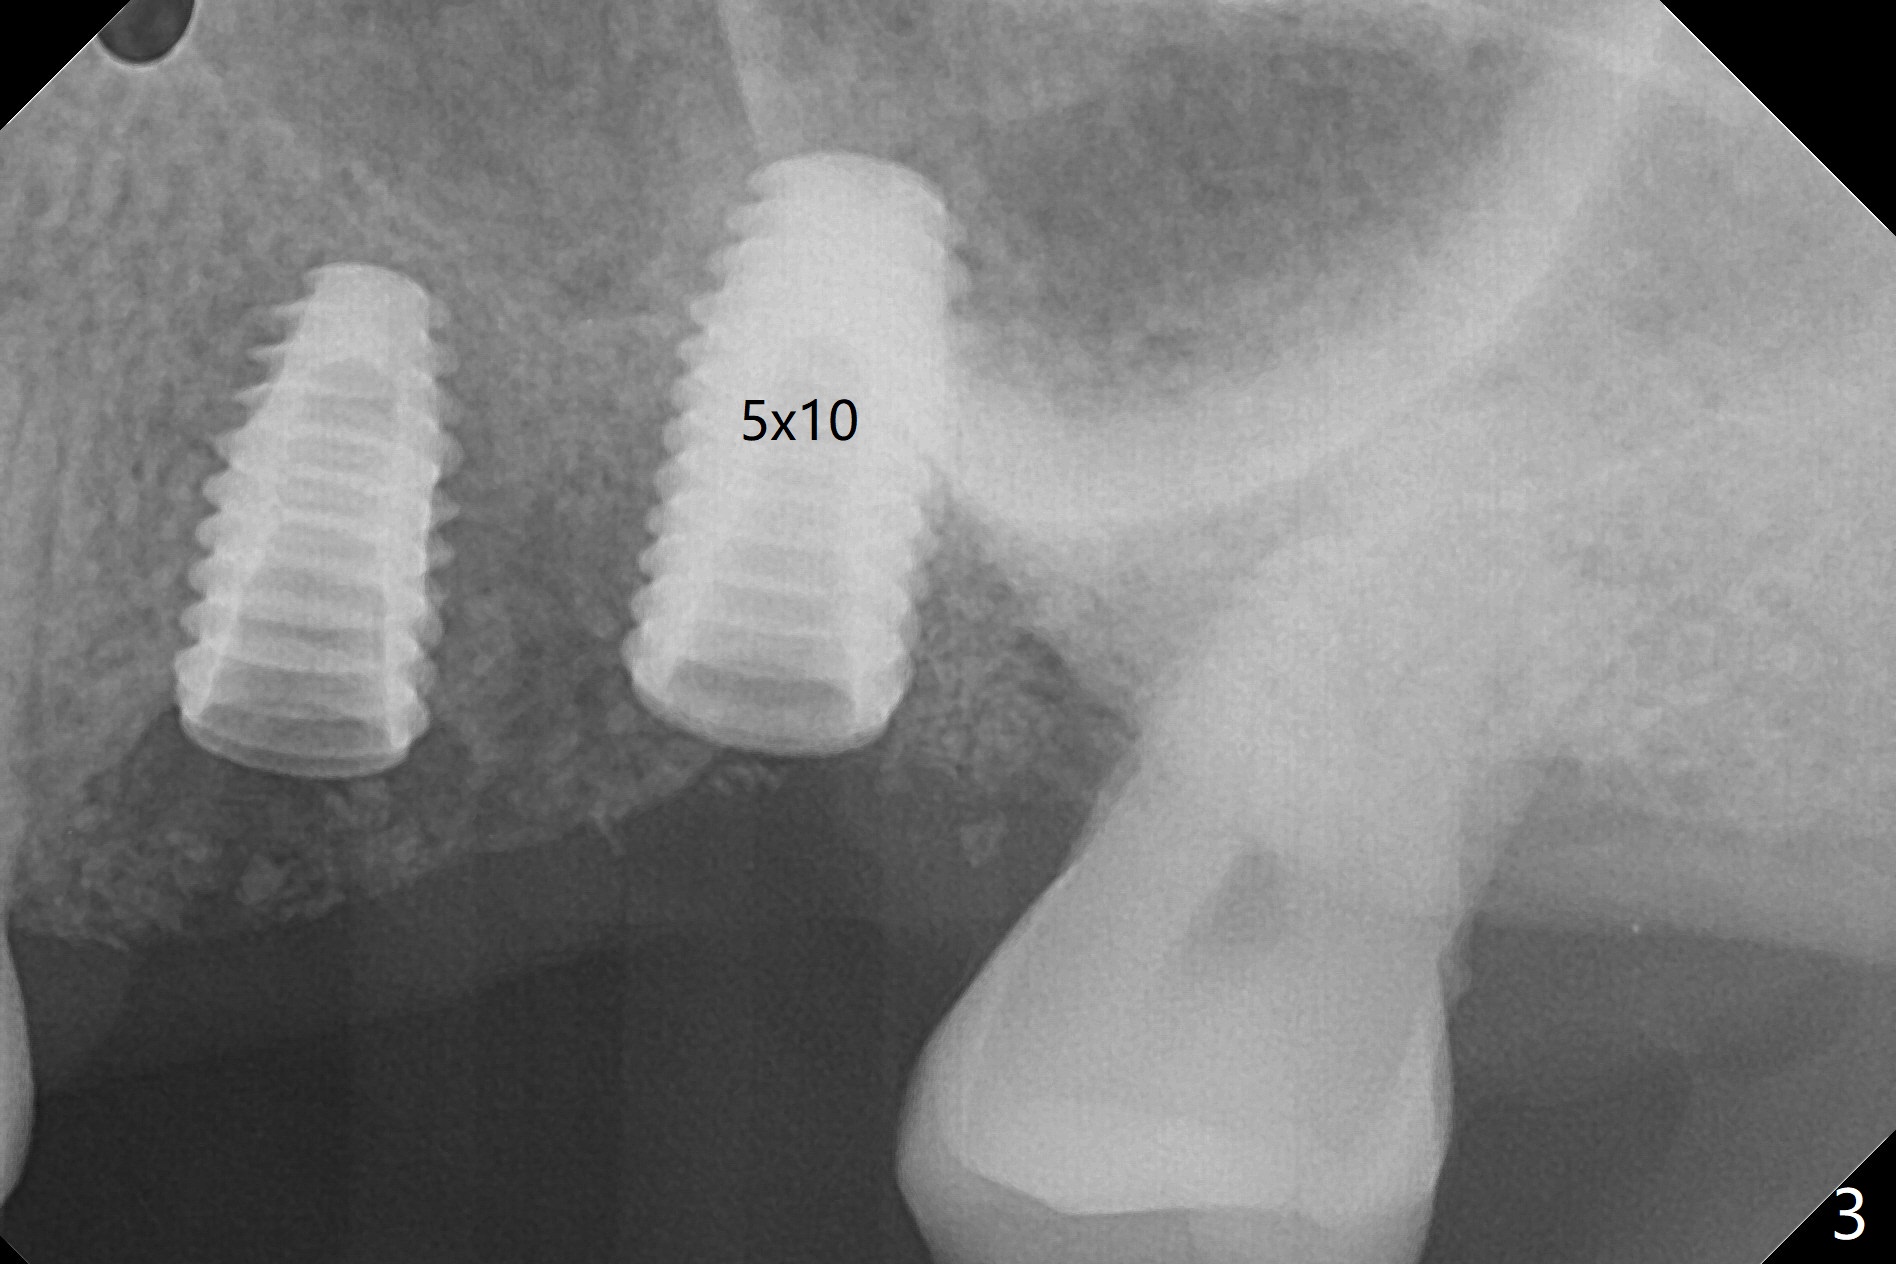

Fixture mount does not fit at #13 as an anchor. After 3.5x7.3 mm drill with 10.5 mm offset at #14, sinus lift drills (3.6x18 and 19 mm) are used. The sinus floor is intact. A 9 mm offset should be used. Following 4.0x10 mm dummy implant is placed for ~ 8.5 mm, the sinus floor is perforated while the sinus membrane is intact. After water lift, PRF membrane and allograft are inserted and pushed upward with the 4.0x10 mm dummy implant for ~ 10 mm (Fig.1). One more piece of PRF membrane and bone graft are lifted with a 4.5x10 mm dummy implant. A small dose of bone graft is elevated with a definitive implant (Fig.2,3, 5x10 mm). Is there enough bone to cover the apical part of the implant when the latter heals? When the patient returns for restoration 4.5 months postop, local oral hygiene is not good with light gingival erythema. There is tenderness when the healing abutment is being removed. It appears that osteointegraton is to occur; the mesial bone density is low (Fig.4 *). Healing abutment should be not placed when sinus lift repeatedly fails. In fact the implant is removed with the healing abutment 6.5 months postop. The buccal plate is missing, while the sinus floor is intact. Ossogen is placed, covered by Osteogen plug and sutured with PGA (Fig.5). The buccal plate remains concave 8 days postop (Fig.6 B). In the 4th trial, incision will be made, flaps dissected extensively with suture fixation. The existing guide is used to start osteotomy with point drill, followed by bone expansion. Reload the guide to place a narrower implant 4 or 4.5 mm with cover screw, and place sticky bone buccal. The latter is covered with PRF and suture. If stability is insufficient, perforate the sinus floor. Place a cemented abutment at #13 to hold periodontal dressing. Use profile drill if needed.Return to Upper Molar Immediate Implant, Trajectory II Xin Wei, DDS, PhD, MS 1st edition 08/13/2019, last revision 02/13/2021